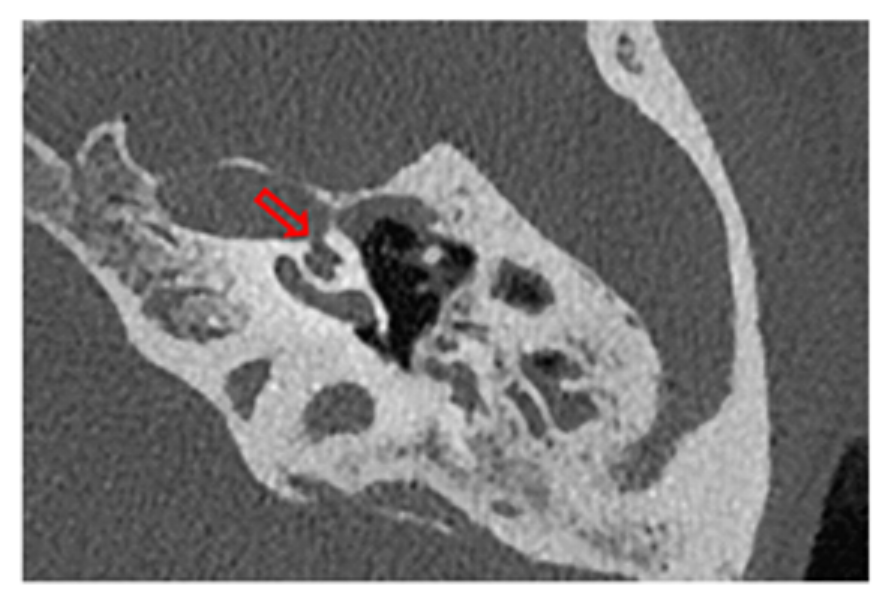

- Imaging studies: Thin-section helical CT scans (SOMATOM CT Scanner Dual Source and Single Source, Siemens Healthineers, Erlangen, Germany) with a slice thickness of 0.4 mm were employed to determine the dehiscences. To avoid selection bias and ensure rigorous criteria, only patients who presented at least one objective auditory fluctuation in pure-tone audiometry and/or those with a minimum of two episodes of spontaneous vertigo lasting longer than 20 min were selected for this test. These symptoms were used as they are considered reliable indicators of potential underlying pathologies that justify the use of advanced imaging techniques [1,8]. If these criteria were met, a 3T MRI (MAGNETOM Skyra, Siemens, Erlangen, Germany) was performed using a T2-FLAIR sequence for four hours after intravenous gadolinium administration to assess the presence of cochlear and vestibular EH.

Third window syndrome ![]() | Type I (SSCD) | 76 | 88.37% | Unsteadiness: 34.88% Hearing loss: 32.56% Fullness/tinnitus: 22.09% Vertigo attack: 19.76% Autophony: 16.27% Tullio/Hennebert: 9.30% Falls: 5.81% | 28 dB | Yes (n = 24) | Yes (n = 55) | Yes (n = 6) | Increased oVEMP amplitude at 4 kHz |

![]() Other otic capsule dehiscences | Type II Cochleo–carotid and PSC–jugular vein | 2 | 2.32% | Hearing loss: 100% Autophony: 66.67% Unsteadiness: 50% Vertigo attack: 33.33% Fullness/tinnitus: 16.67% Tullio/Hennebert: 16.67% Falls: 16.67% | 52 dB | No | No | Yes (n = 1) | Type B timpanogram with absent stapedial reflex |